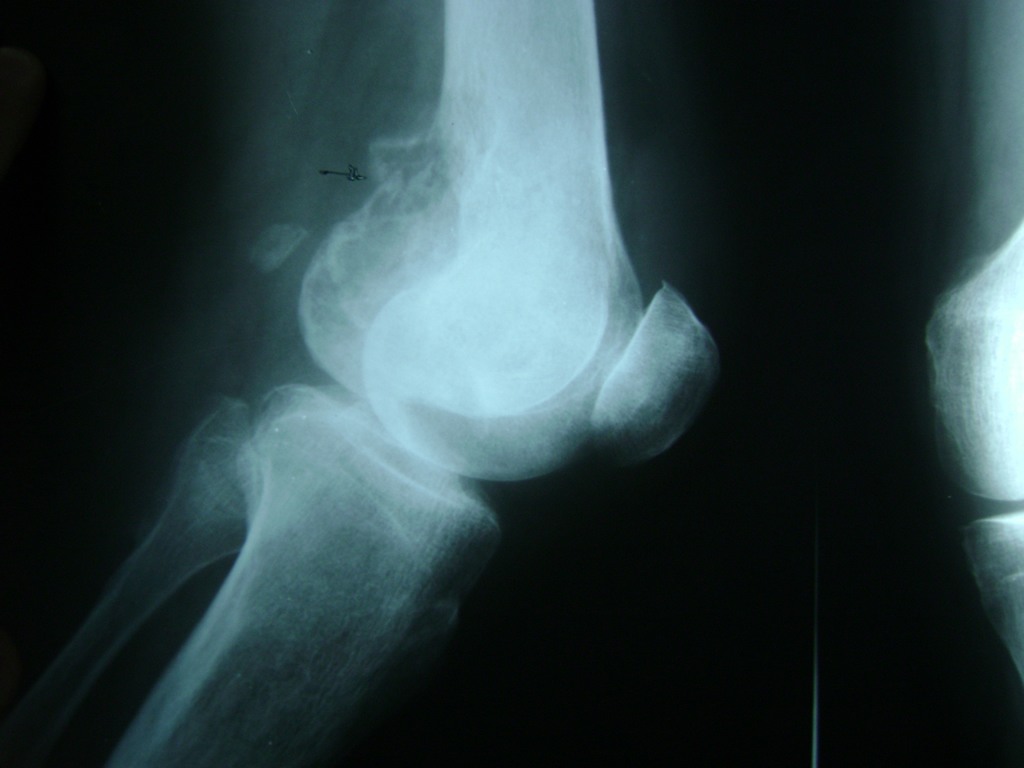

Calcaneo - Rodilla

La artroscopia de rodilla es un cirugía en el cual la estructura interna de la articulación es examinada ya sea para realizar un diagnostico o para realizar un tratamiento, este procedimiento se realiza utilizando un instrumento parecido a un pequeño tubo llamado artroscopio.